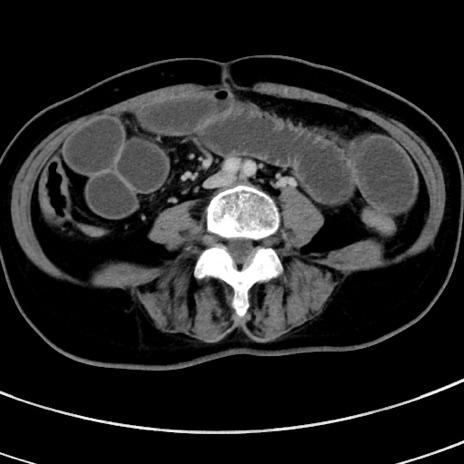

症例9(横断像)

【症例】 60歳代女性

【主訴】むかつき、みぞおちの痛み

【現病歴】3日前よりむかつきがあり、食事がとれない。

【既往歴】糖尿病

【身体所見】発熱なし、心窩部圧痛軽度あるも、腹膜刺激症状なし。

【データ】WBC 7400、CRP 1.92